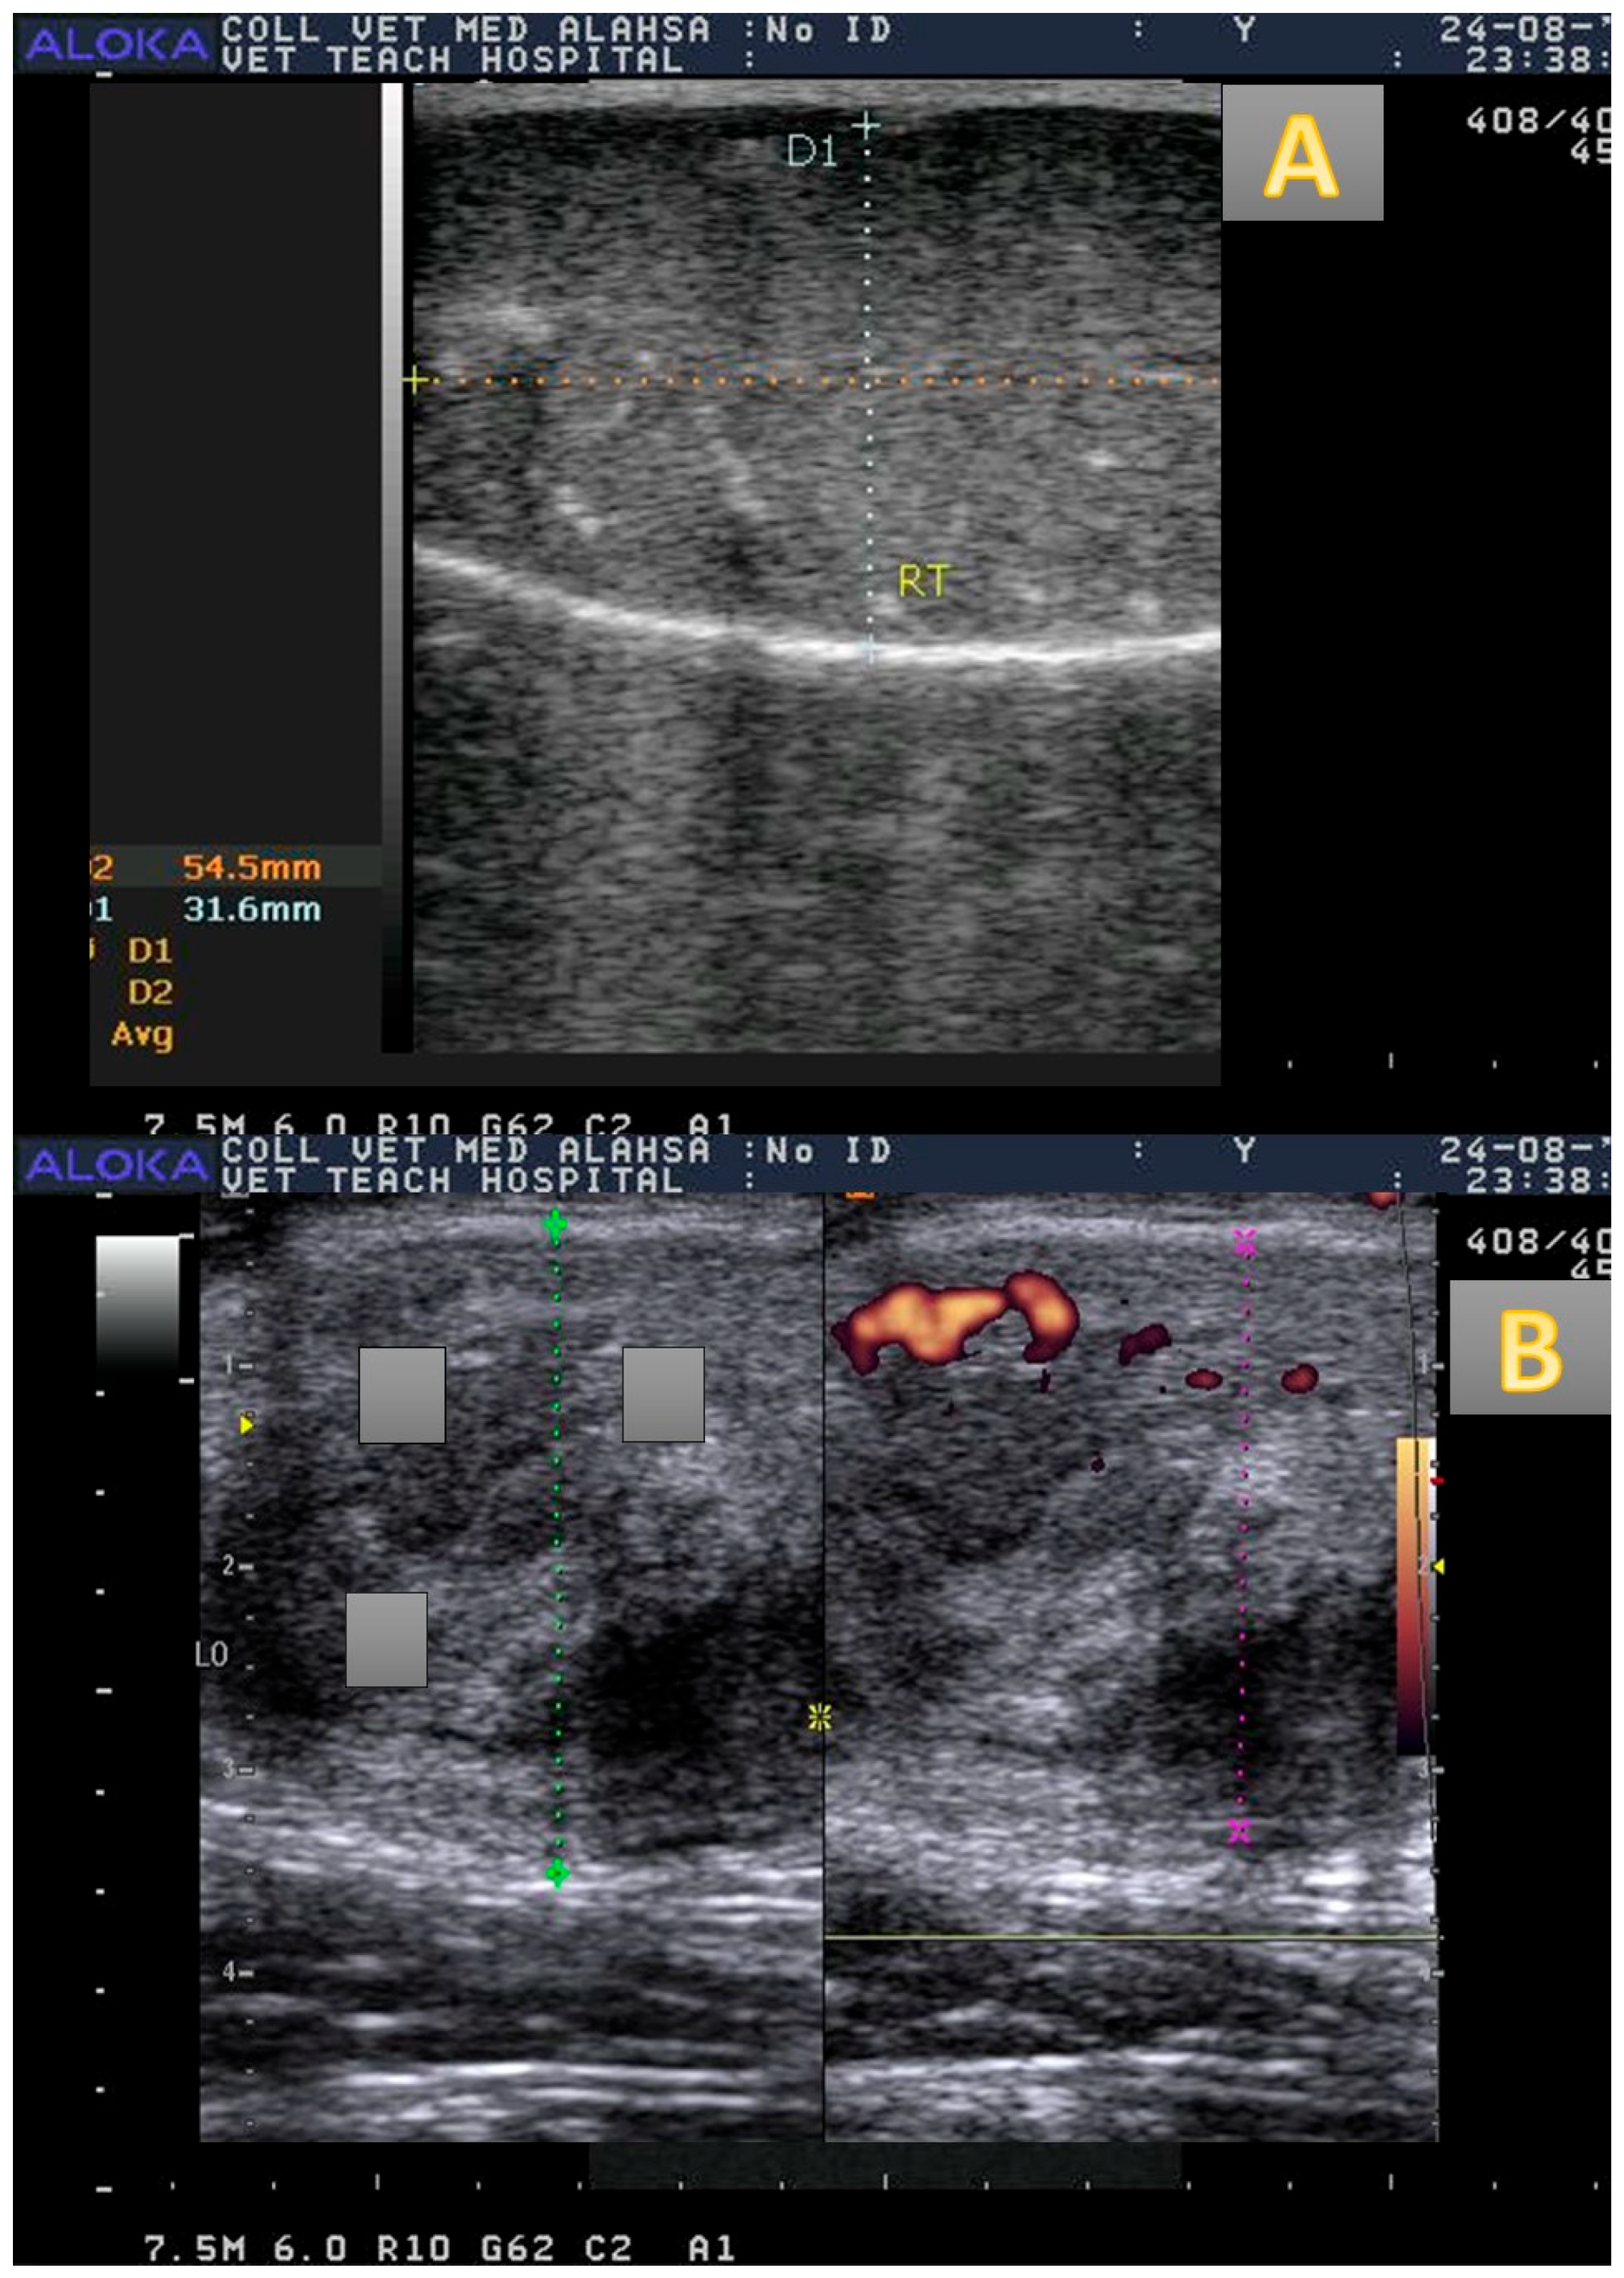

3.2. Testicular Vascularization

3.3. Testicular Morphometry and Echogenicity